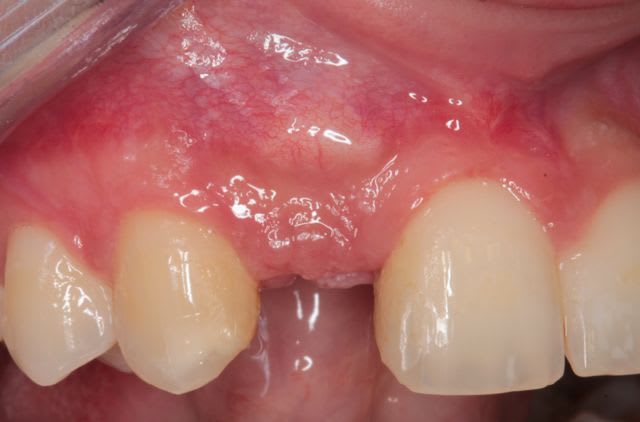

la suite et le début:

scan pré op: pas bcp d'os dispo au niveau de 46 47, y'a fallu aller plus loin derrière

la 11: voir son axe et le peu d'os autour en vestibulaire

photo de la cica à quelque mois

bientôt scan et pose de l'implant